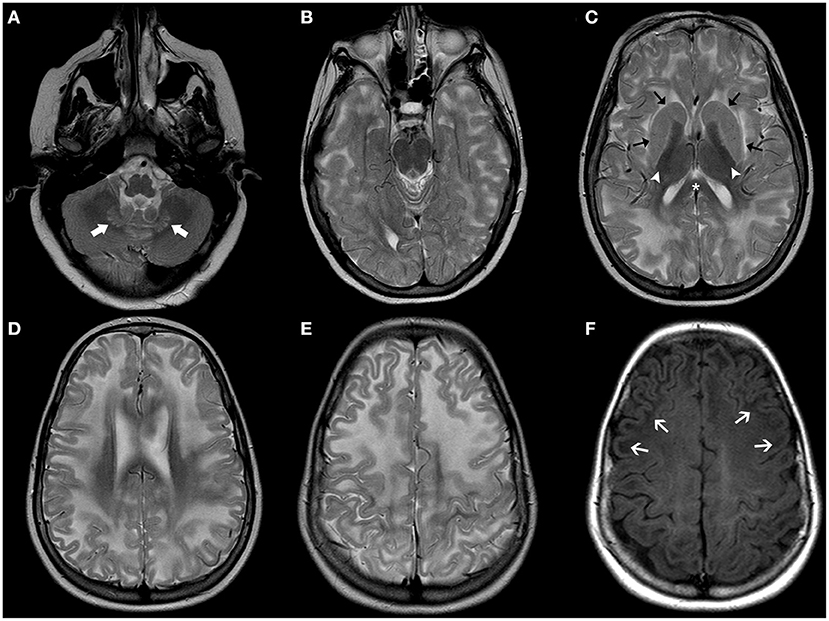

Megalencephalic leukoencephalopathy with subcortical cysts (MLC) is a neurodevelopmental disorder caused by biallelic mutations in the MLC1 gene in two-third of cases (MLC1) (89). It may also be due to biallelic (MCL2A) or more rarely monoallelic variants (MCL2B) in HEPACAM, encoding GlialCAM which is an MLC1-interacting protein in junctions between astrocytes (90). The typical presentation of MLC includes macrocephaly (between +4 and 6 SD) during the first year of life in a child with mild DD who develops gradual motor deterioration with ataxia and spasticity (60). However, the clinical course is not as severe as the one observed in Alexander and Canavan disease. Seizures are common whereas cognition is usually preserved. The neuroradiological hallmarks include diffuse, confluent areas of white matter signal abnormality with relative sparing of the corpus callosum and associated brain swelling as well as subcortical cysts and/or areas of near-cyst white matter rarefaction predominantly located in the anterior temporal and frontopolar regions (Figure 7). White matter edema decreases with time leading to atrophic changes. Clinical presentation and neuroradiological findings in MLC1 and MCL2A (classic MLC) overlap, with a common progressive course. In addition, affected patients usually demonstrate a double-line signal abnormality in the posterior limb of the internal capsule as well as cerebellar involvement. On the other hand, MCL2B shows a milder phenotype with preservation of the motor function as well as sparing of the cerebellar white-matter and posterior limb of the internal capsule. Moreover, it usually presents neuroradiological signs of stability or improvement over years (91).

Figure 7. Imaging characteristics of Megalencephalic Leukoencephalopathy With Subcortical Cysts (classic form). Axial T2WI (A–D), axial (E,F), and coronal (G) T1WI, and coronal FLAIR (H) performed in an affected boy at 1.8 years of age show diffuse, bilateral, and symmetric cerebral white matter hyperintensity including the subcortical white-matter/U-fibers, leading to brain swelling and effacement of the cortical sulci. There is a characteristic double-line signal abnormality in the posterior limb of the internal capsule (white arrows), i.e., a residual central dark line surrounded by two strands of hyperintensity in this location. Also note the typical areas of cystic-like white-matter rarefaction in the temporal-polar regions on T1WI and FLAIR (thick white arrows).